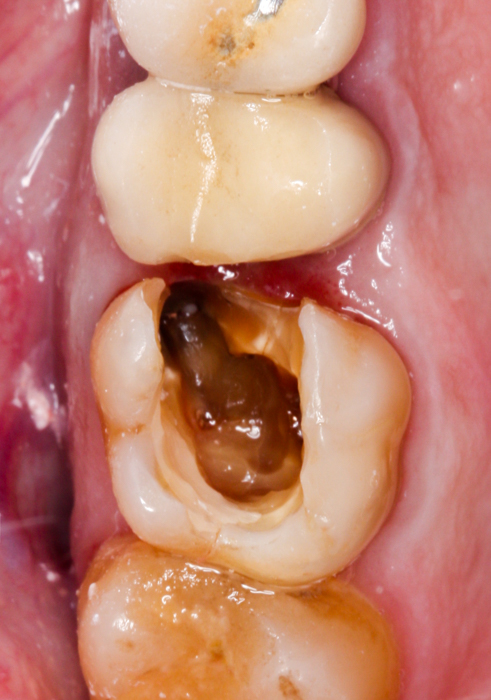

Tak właśnie było w przedstawionym poniżej przypadku – w korzeniu policzkowym bliższym zęba uprzednio leczonego kanałowo znajdował się bardzo głęboko schodzący poddziąsłowo ubytek próchnicowy, sięgający niemal brzegu kości, ponadto torbiel okołowierzchołkowa i widoczny, spowodowany być może stanem zapalnym wokół zęba, odczyn w zatoce szczękowej, manifestujący się pogrubioną błoną śluzową. Po dokładnej diagnostyce radiologicznej wspartej badaniem tomograficznym CBCT i omówieniu z pacjentem wszystkich możliwych wariantów wraz z wynikającymi z nich korzyściami i ryzykiem, wybór padł na radektomię.

W znieczuleniu miejscowym, z użyciem mikroskopu, maleńkim wiertłem odcięty został uszkodzony korzeń tak, aby w możliwie najmniejszym stopniu uszkodzić fragmenty zęba, które mają pozostać w jamie ustnej pacjenta oraz otaczającą je kość. Następnie, niezwykle ostrożnie, usunięto odpreparowany korzeń, wyłuszczono w całości torbiel i założono szew stabilizujący powstający w zębodole skrzep. Pozostałą część zęba zabezpieczono materiałem kompozytowym do czasu, gdy będzie możliwe wykonanie powtórnego leczenia kanałowego i ostateczna odbudowa części koronowej.